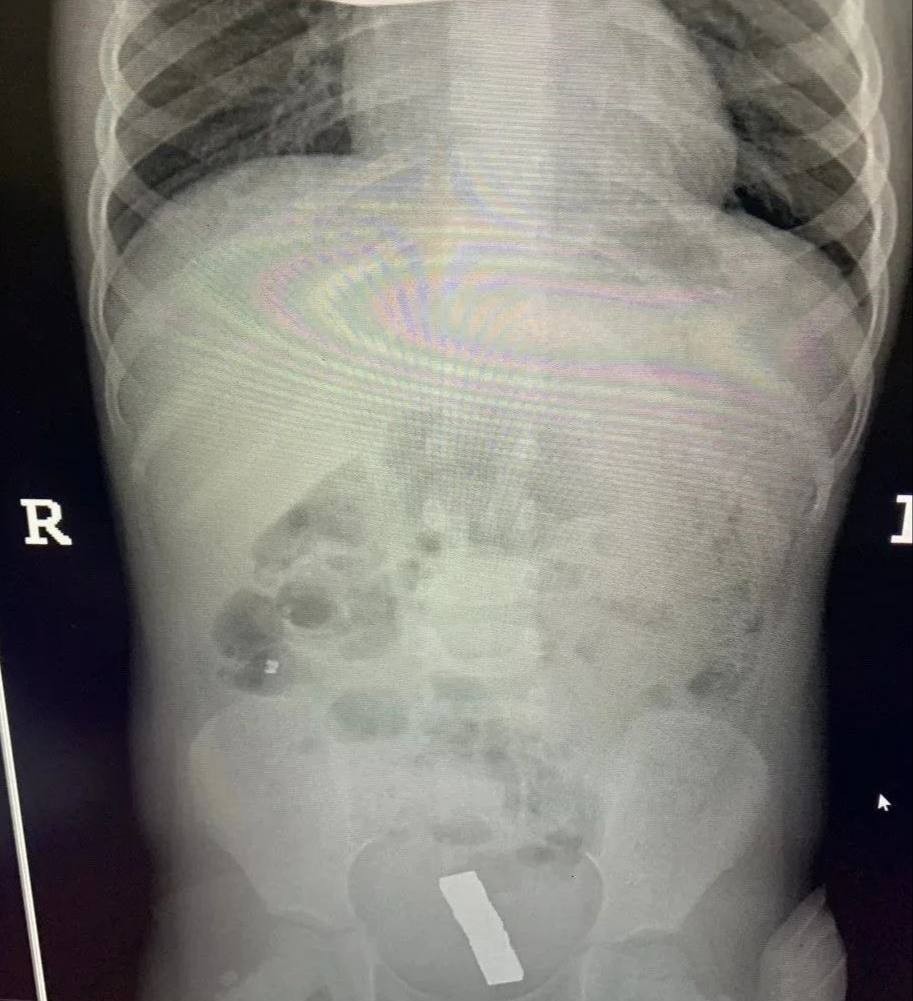

Инцидент произошел в Балашихе — малолетнюю пациентку с жалобами на острую боль в животе доставила в больницу бригада скорой помощи. Обследование показало, что внутри у ребенка большое количество металлических инородных тел. Девочку немедленно отправили на операционный стол.

Врачи приняли решение обойтись без полостного вмешательства. Через крошечные проколы специалисты аккуратно извлекли 20 магнитов из организма ребенка — они успели притянуться друг к другу и прожечь стенку кишки насквозь. Пять штук и вовсе мигрировали в область малого таза.